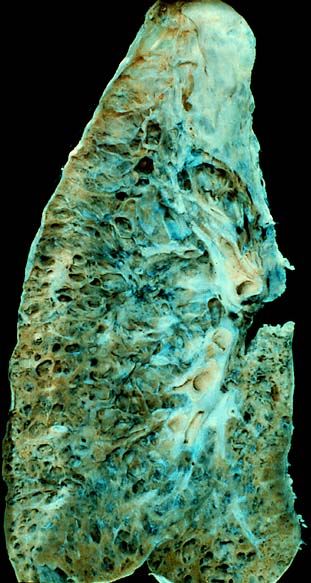

Tuberculosis (TB)

As a result of first-time exposure to aerosolized Mycobacterium tuberculosis, primary tuberculosis (TB) develops.

Tuberculosis (TB) results in the hilar lymph nodes undergoing fibrosis and calcification to produce a Ghon complex as well as localized, caseating necrosis of the lung.

Tuberculosis (TB) usually occurs at the lung’s apex due to the high oxygen tension in that region of the lungs.

Tuberculosis (TB) creates a cavitary foci of caseous necrosis and has the potential to cause tuberculous bronchopneumonia or miliary pulmonary tuberculosis.

Histology of tuberculosis (TB) shows caseating granulomas, and positive acid-fast bacilli (AFB) stain.